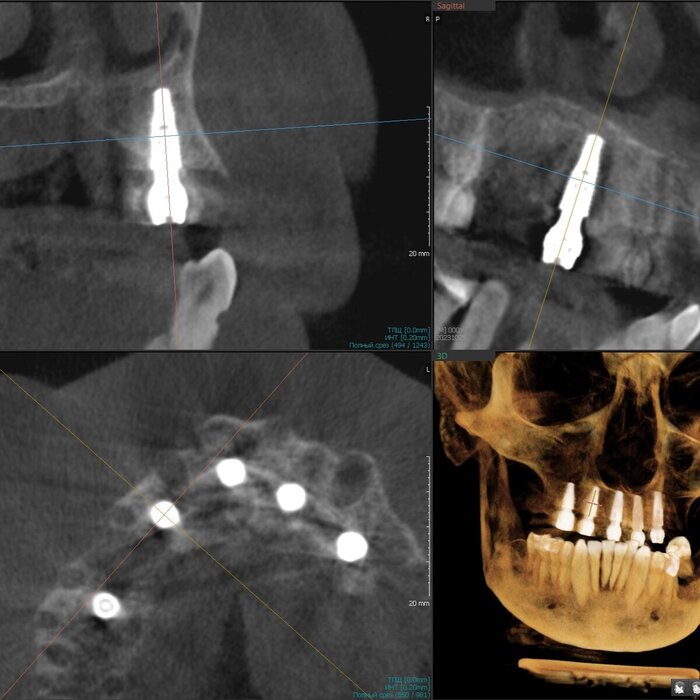

Как же всё-таки у нас происходит это мероприятие? Так как мы вмешиваемся в другую область нашего тела, то стоматолог должен быть хоть немного лором. Разумеется, всё начинается с обследования, которое включает в себя трехмерный снимок, который, в идеале должен захватывать не только зубы и область наращивания, но и носовые ходы с устьями гайморовых пазух и прочими загогулинами, то есть, так называемый остиомеатальный комплекс.

Поэтому кастрированный снимок, где видна только область установки будущего имплантата не прокатит. Тем более в центрах КТ такой снимок стоит дороже классической КТ рублей на 200. И стоит ли экономить?

Анализируя снимок, мы должны принять решение о том можно ли делать синус-лифтинг или отправить его на консультацию к лору. Если всё хорошо, то планируем операцию.